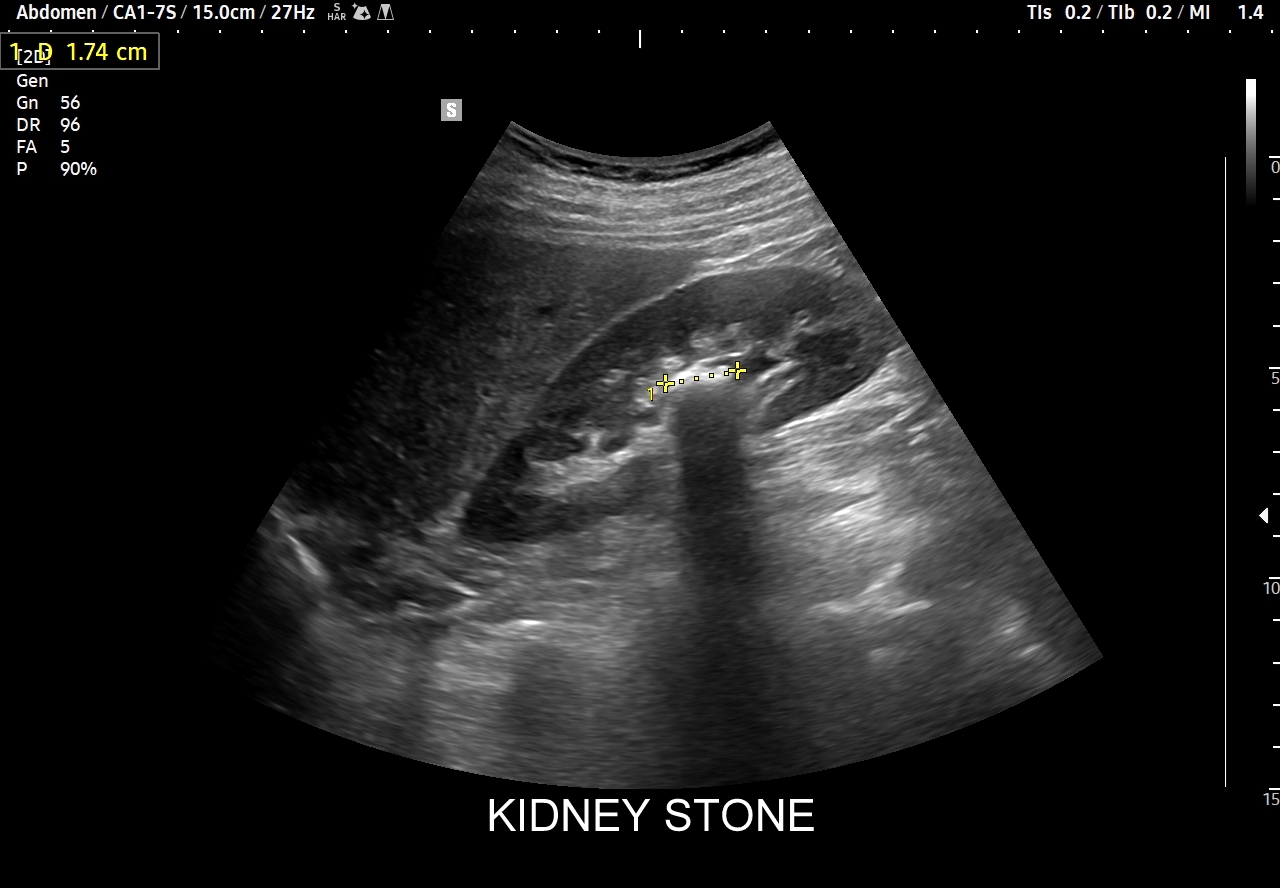

Badania obrazowe służące wykrywaniu kamicy moczowej to badanie RTG, CT, lecz przede wszystkim badanie USG. W badaniu USG nerek w prezentacji B kamica nerkowa widoczna jest w sytuacji, gdy złogi są odpowiednio uwapnione, odpowiednio duże oraz nie zlewają się z zatoką tłuszczową miedniczki nerki. Zasadniczo złogi w trybie B będą widoczne wyraźniej, gdy położone są w miąższu nerki; z kolei w miedniczce nerkowej, gdy są na tyle duże, że dają artefakt cienia. Czasem w celu uwidocznienia złogu przydatne jest wyłączenie wspomagania typu x-beam.

Ważnym trybem pomocniczym jest color-Doppler, w którym to trybie uzyskuje się tzw. artefakt migotania, często nawet na bardzo drobnych złogach niewidocznych w trybie B. Uzyskanie efektu migotania jest niestety zależne o jakości aparatury USG, a także od ustawień Dopplera i software’u.